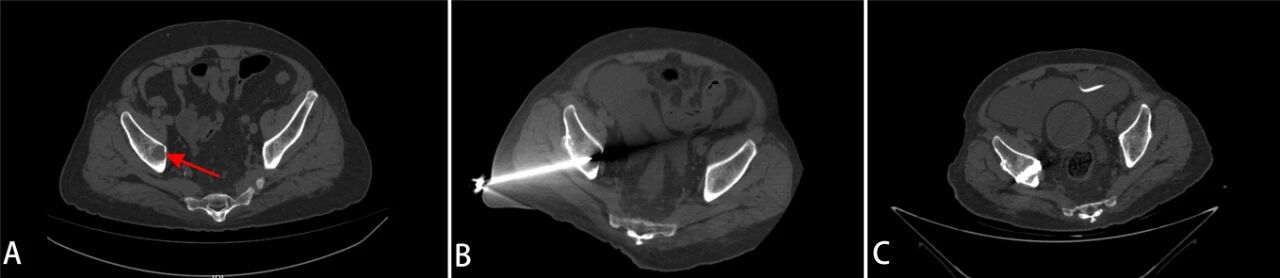

术前髋臼破坏(A),消融针经通道置入病灶(B),骨水泥注入骨质缺损处(C)

第一步:肿瘤消融。在CT引导下,微创介入科主任胡鸿涛通过一根细长的消融针,精准置入病灶中心,利用热消融技术灭活“烫死”肿瘤细胞,从根源上处理局部病变。

第二步:骨水泥成形。消融后,骨与软组织科冯和林主任利用同一穿刺路径向被破坏的骨空腔内注入医用骨水泥。骨水泥迅速凝固后,像混凝土一样强化骨骼结构,恢复髋臼的承重功能。